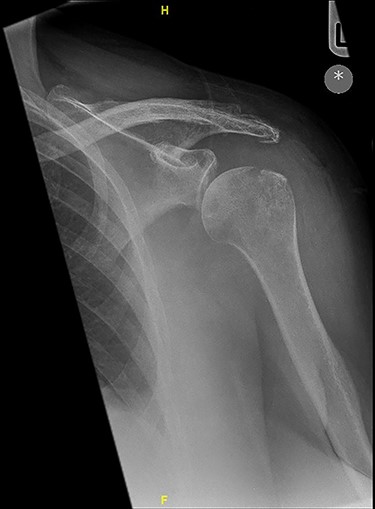

X-ray imaging showed degenerative changes in the glenohumeral and acromioclavicular articulations.

X-ray imaging showed degenerative changes in the glenohumeral and acromioclavicular articulations with inferior displacement of the humeral head.